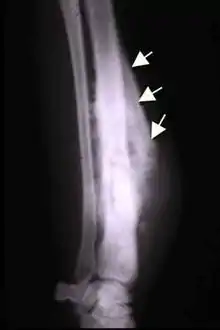

The Codman triangle

The Codman triangle (previously referred to as Codman's triangle) is the triangular area of new subperiosteal bone that is created when a lesion, often a tumour, raises the periosteum away from the bone.[1] A Codman triangle is not actually a full triangle. Instead, it is often a pseudotriangle on radiographic findings, with ossification on the original bone and one additional side of the triangle, which forms a two sided triangle with one open side. This two sided appearance is generated due to a tumor (or growth) that is growing at a rate which is faster than the periosteum can grow or expand, so instead of dimpling, the periosteum tears away and provides ossification on the second edge of the triangle.[2] The advancing tumour displaces the periosteum away from the bone medulla. The displaced and now lateral periosteum attempts to regenerate underlying bone. This describes a periosteal reaction.

The main causes for this sign are osteosarcoma, Ewing's sarcoma, eumycetoma, and a subperiosteal abscess.[3][4]